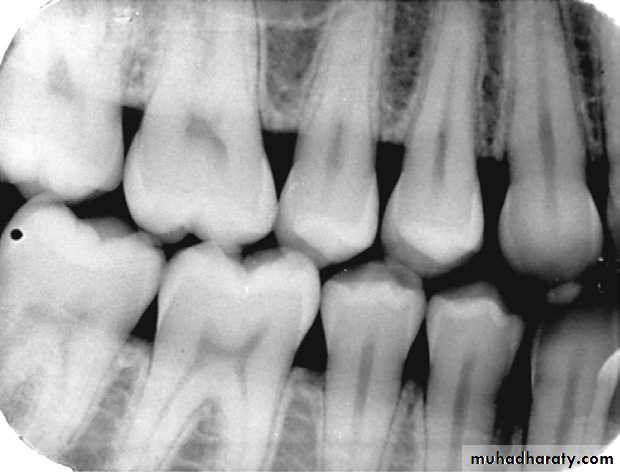

Subgingival calculus that appears as irregular radiopaque projections in the maxillary anterior region.

Calculus that appears as sharp, pointed radiopacities along the surfaces of mandibular anterior teeth.